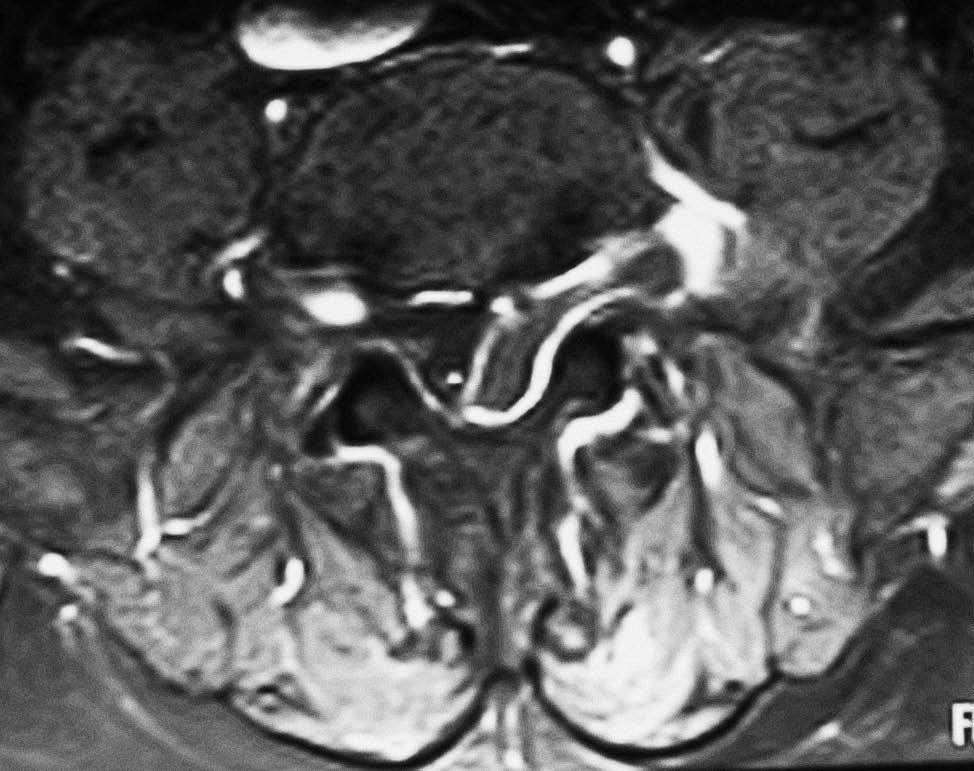

Fig. 4.--RM secuencia SE pT1 con supresión grasa espectral, tras administración de gadolinio intravenoso. Corte axial. La lesión presenta realce marginal compatible con la presencia de tejido cicatricial o de granulación perilesional. El centro no presenta realce.